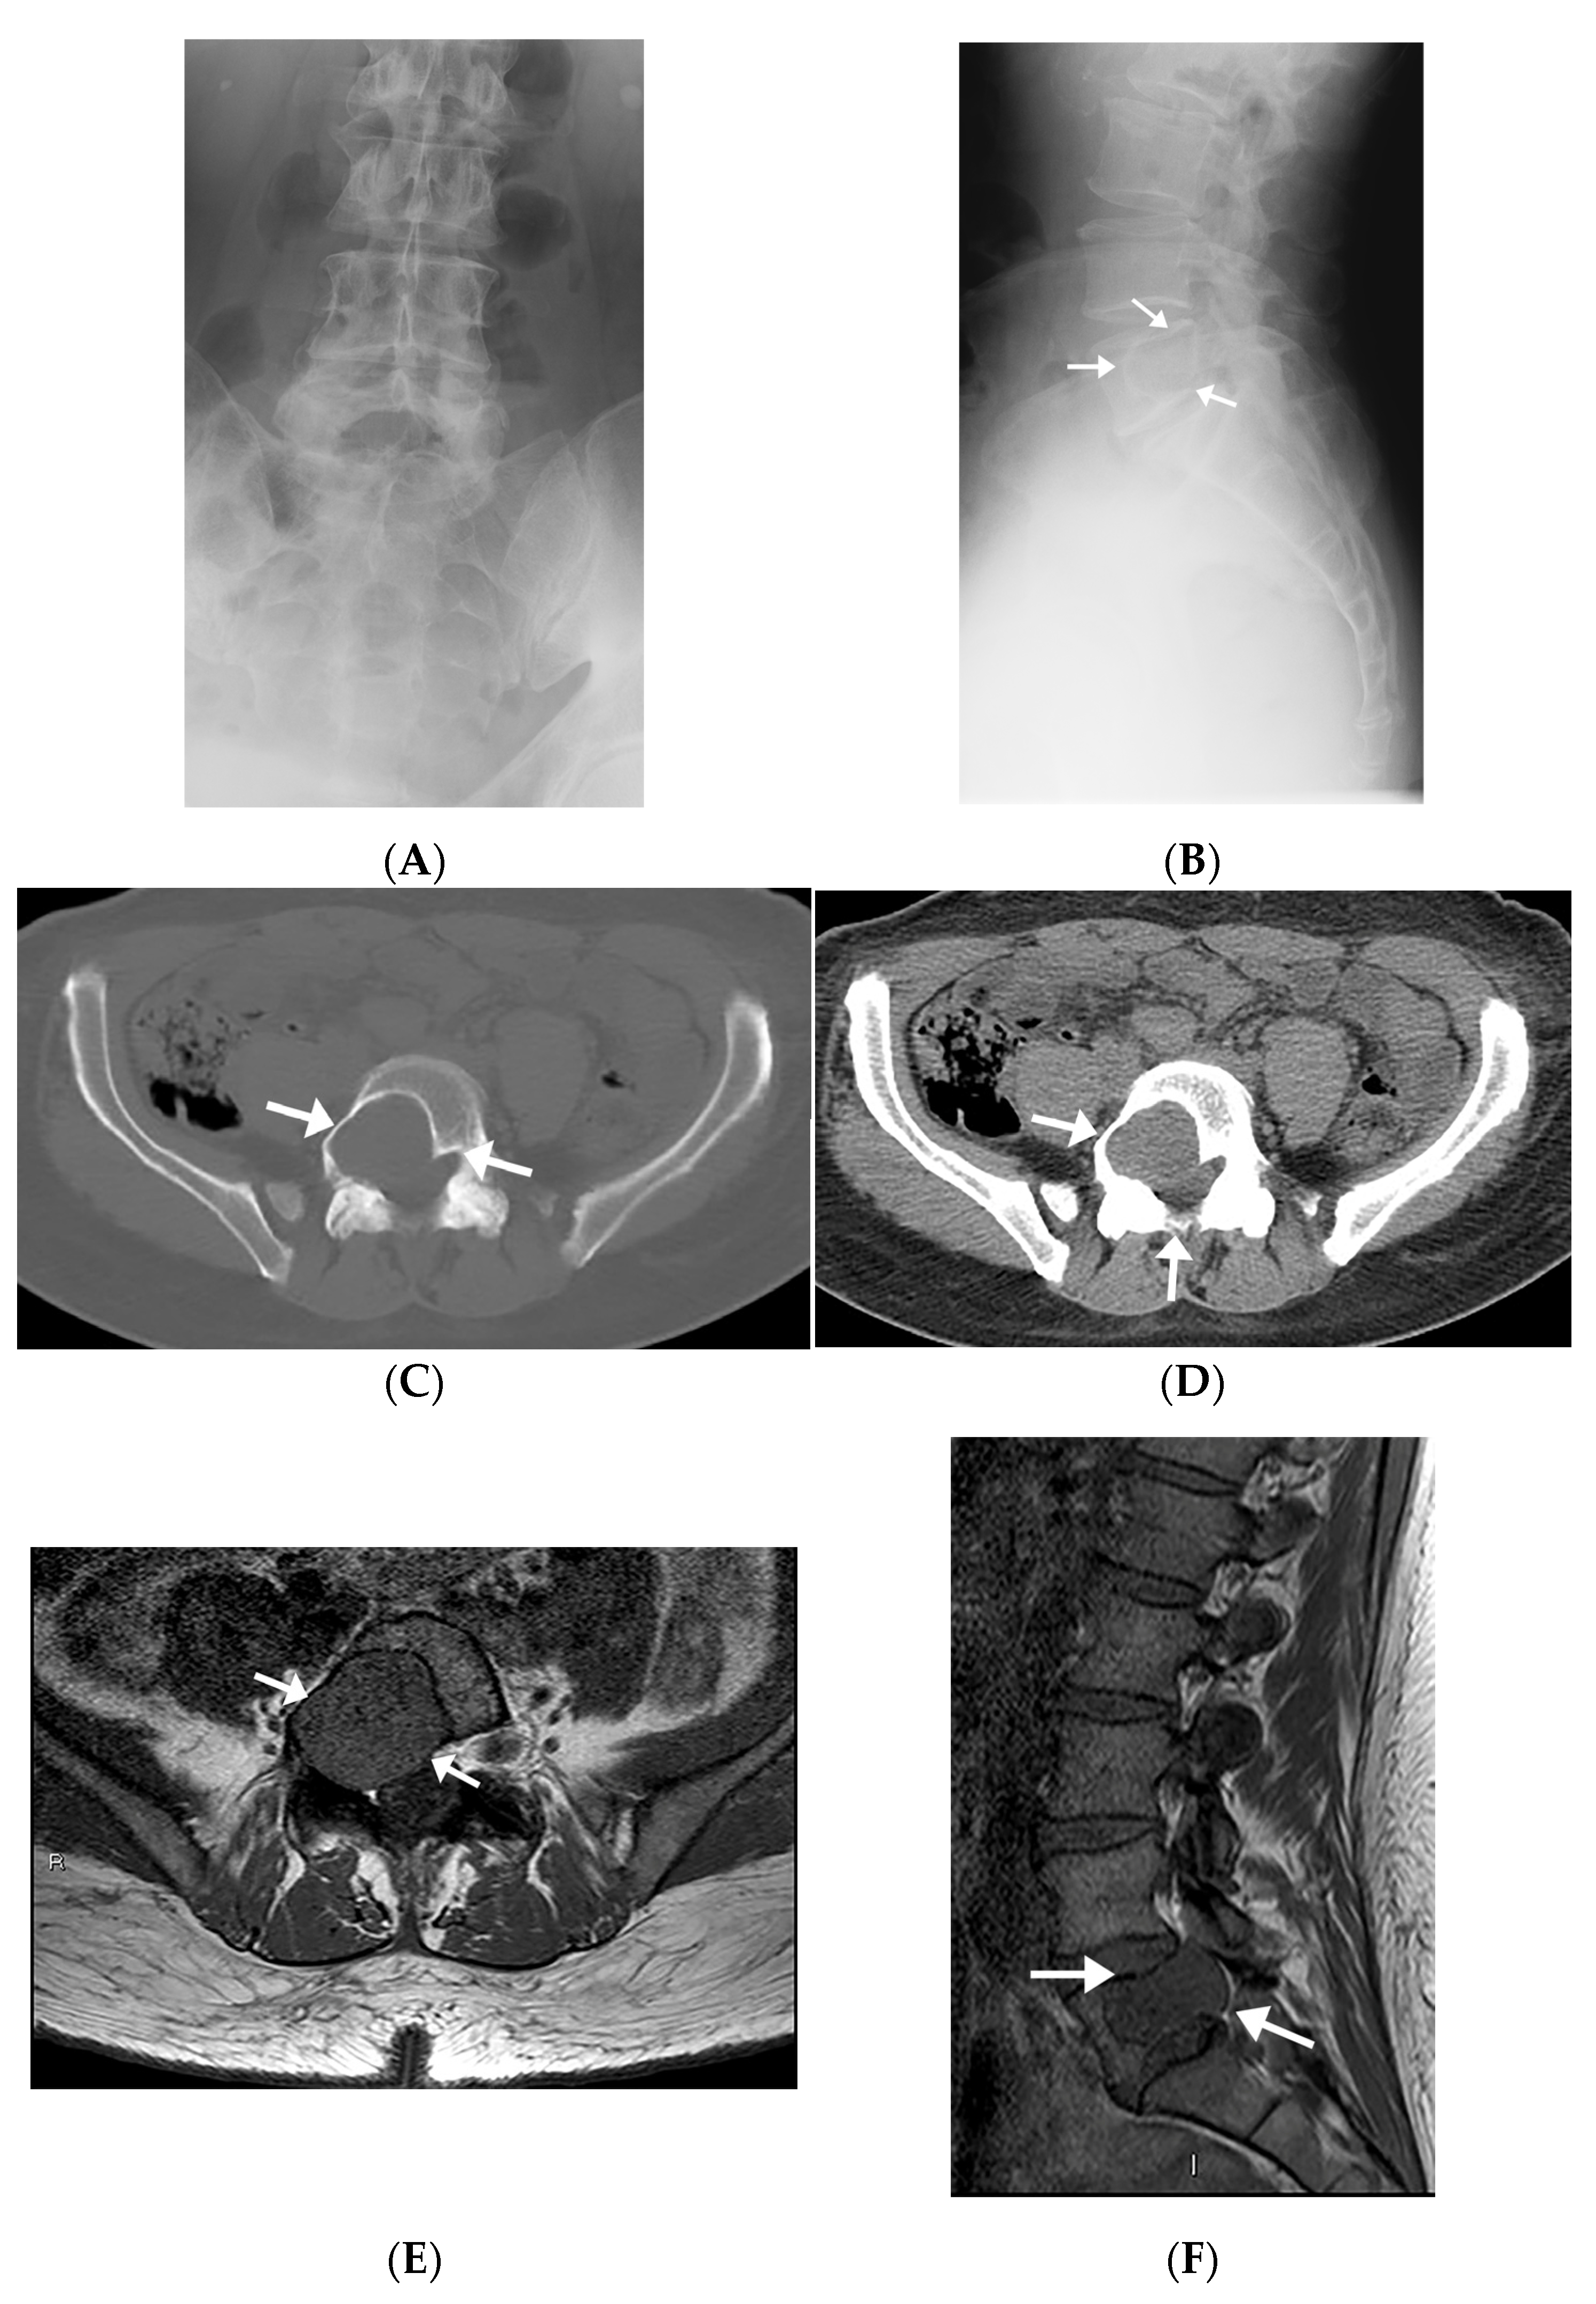

Radiographs were available on four patients. One of these only had a postoperative radiograph in which the lesion was occult. Other radiographs demonstrated geographic lytic lesions with sclerotic borders (Figure 2A,B).

Figure 2.

Radiographic, MR, and CT imaging appearances of intraosseous schwannoma in a 57-year-old man involving the L5 vertebral body and invading right L5 neural foramen. (A,B) The mass is occult on an AP radiograph (A), but the lateral radiograph (B) shows a large lobular lytic lesion with sclerotic margins. (C,D) Axial CT images in bone (C) and soft tissue (D) windows show an expansile lytic lesion in the right aspect of the L5 vertebral body extending into the pedicle and encroaching upon the right neural foramen and right lateral recess (arrows). (E,F) The mass extends into the right pedicle, encroaching upon the right neural foramen and right lateral recess and has a similar-to-slightly-lower signal relative to the muscle on axial (E) and sagittal (F) T1-weighted images (arrows).

3.1.3. Computed Tomography

All patients had CT images available. Four patients underwent diagnostic CT studies, while the other two had preprocedural CT images obtained during the CT-guided biopsy. Imaging findings mostly included expansile intraosseous lytic lesions extending into adjacent spaces, including the neuroforamina, epidural space, and central spinal canal (Figure 2C,D). There was one case of a locally aggressive tumor extending anteriorly into the pelvis and posteriorly into the epidural space (Figure 3). The masses were characterized on imaging as heterogeneous, expansile lesions with centrally hypodense areas and peripheral rims of sclerosis.

3.1.4. Magnetic Resonance Imaging

All IOSs demonstrated consistent signal characteristics on MRI with a low-to-intermediate signal intensity to muscle on T1-weighted images (T1-WI) and heterogenous hyperintense signal intensity on fluid-sensitive sequences. Extra-osseous extension was frequently demonstrated, including invasion into neural foramina with displacement of adjacent nerve roots (Figure 2E,F) and involvement of the epidural space. There was posterior osseous extension from vertebral bodies into the pedicles and spinous processes. There was avid post-contrast enhancement with scattered areas of central non-enhancement.